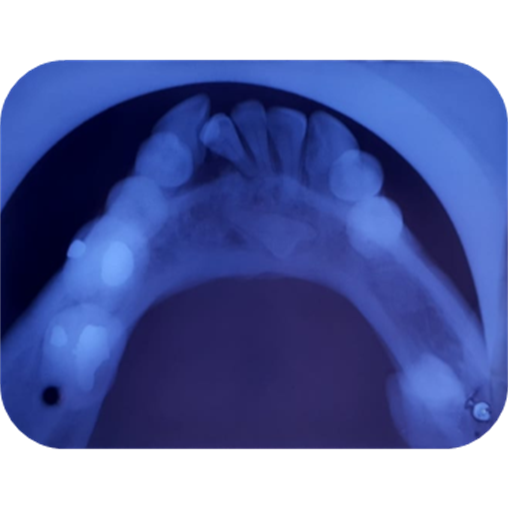

El estudio radiográfico puede evidenciar múltiples sombras radiopacas rodeadas de un halo radiolúcido pertenecientes a un tumor odontogénico CIE10: D164 (odontoma compuesto), localizados en a nivel de los órganos dentarios 4.3; 4.1; 3.1; 3.2; 3.3. También se puede constatar la presencia de una sombra radiopaca que concuerdan con el órgano dentario retenido.

Imagen 4. Oclusal Inferior.